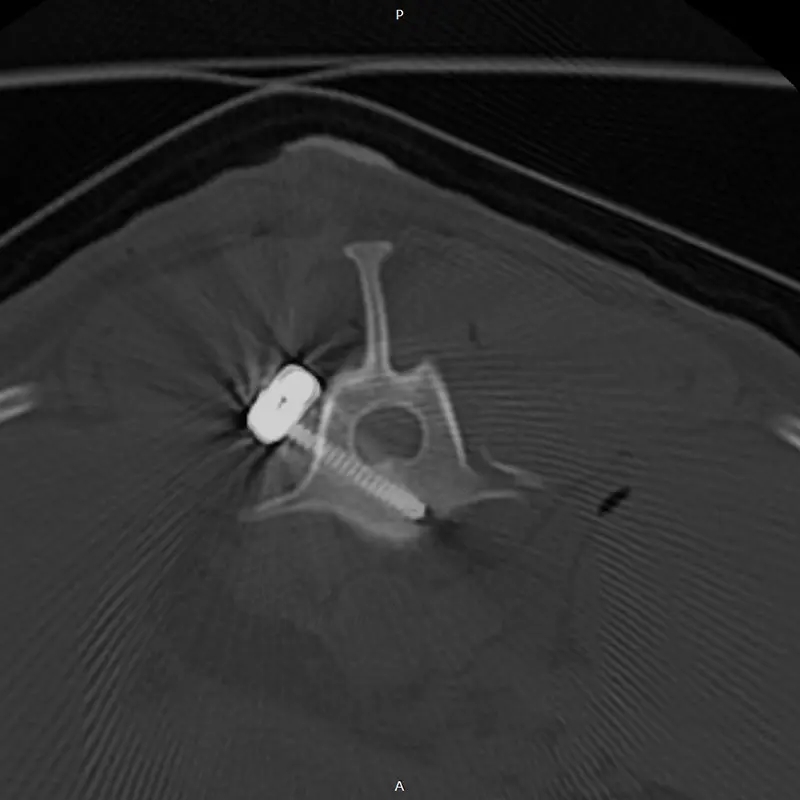

We have been using the system for years, and clinical experience greatly supports its reliability, even in difficult, challenging situations. It is excellent for stabilizing the spine, especially in the thoraco-lumbar region. If the connecting rod is placed ventrally from the articular processes, the screws are placed in the vertebral body at a 45-degree angle at the base of the transverse processes, so that they grip the largest possible bone material. (see CT images). Up to 2 clamps can be attached to a vertebral body from one side. Compared to other, more complex, multi-piece spinal stabilization systems, it is thinner and fits better on the surface of the bone. The screw axis is located ont he side of the axis of the connecting rod (the rod and the screw are not located on top of each other), the clamps can be rotated and slid, so that the largest possible bone stock can be freely accessed during surgery.

In our case, we stabilized the T13-L1 vertebral luxation of a 4-year-old dachshund, where the ligament system of the vertebral body was damaged during a car accident.